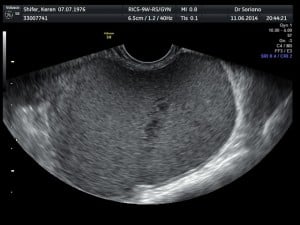

ציסטה בשחלה ציסטות אנדומטריאליות: ציסטה אנדומטריאלית הינה חלק ממגוון הופעה של ממצאים אגניים על רקע אנדומטריוזיס ציסטה בשחלה הנקראת גם אנדומטריומה מופיעה כתוצאה מגדילת מוקדי אנדומטריוזיס ודימום הנאגר בשחלה. כתוצאה מגדילת רירית רחם לע דופן האגן בצמוד לשחלה  בשחלה והופעת דימום מתפתחת ציסטה שחלתית מלאה בדם ישן "ציסטה שוקולדית". ציסטה בשחלה זו עלולה להיות מלווה בתסמיני אנדומטריוזיס.

רקע

נוכחות ציסטה אנדומטריאלית או אנדומטריומה עשויה להיות ממצא מקרי בבדיקת על קול או ממצא המתגלה בעת בירור כאבי אגן כרוניים, כאבים עזים בעת ווסת, כאבים בעת קיום יחסים וכ'. נוכחות ציסטה שחלתית מעל ל 4-5 ס״מ מעידה על חומרת אנדומטריוזיס ולעיתים קרובות מלווה בנוכחות מוקדים נוספים. לעיתים מדובר בציסטות שחלתיות בשתי השחלות אשר כמובן מהווה אתגר כפול. ציסטות אנדומטריאליות גדולות מ 4 ס"מ המלוות בתסמינים או בבעיית פוריות, לא תעלמנה ללא טיפול כירורגי אשר דורש מיומנות וניסיון לשם מניעת נזק שחלתי וגדילה חוזרת.